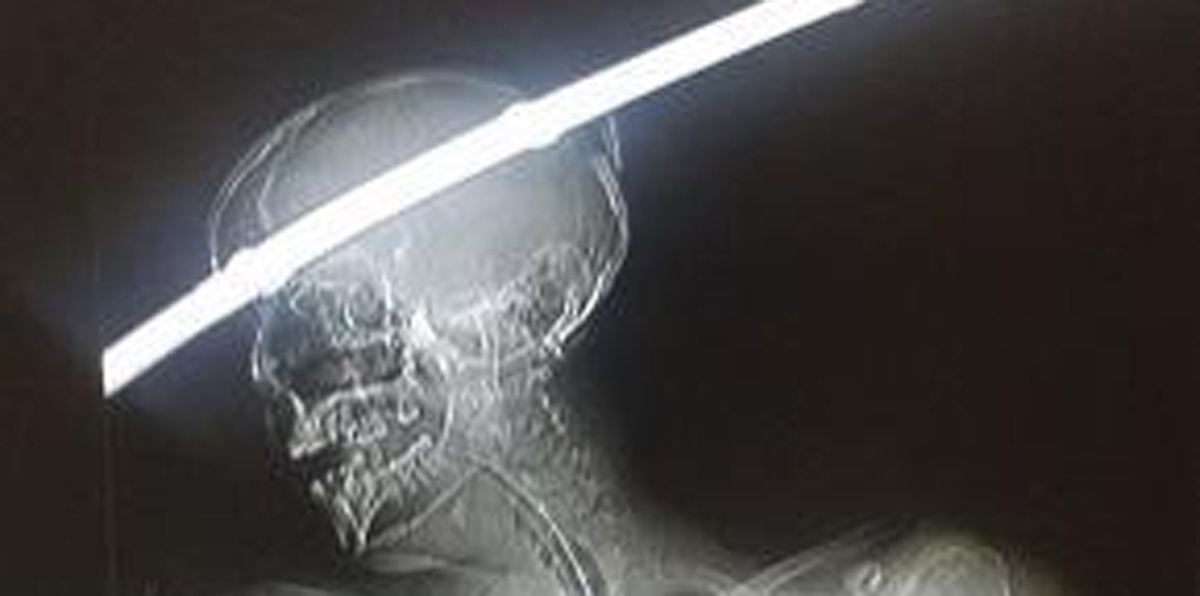

أظهرت صور نشرتها صحيفة "ذا صن" البريطانية، كيف نجا رجل بأعجوبة في الهند بعد أن اخترق جمجمته قضيب معدني طوله متر.

لحسن الحظ، تمكن الأطباء من استخراج القضيب الحديدي، الذي أظهرته الآشعة السينية وهو يخترق جمجمة ودماغ محمد من ناحية إلى أخرى، باستخدام المنظار وجراحة استمرت ساعتين ونصف.